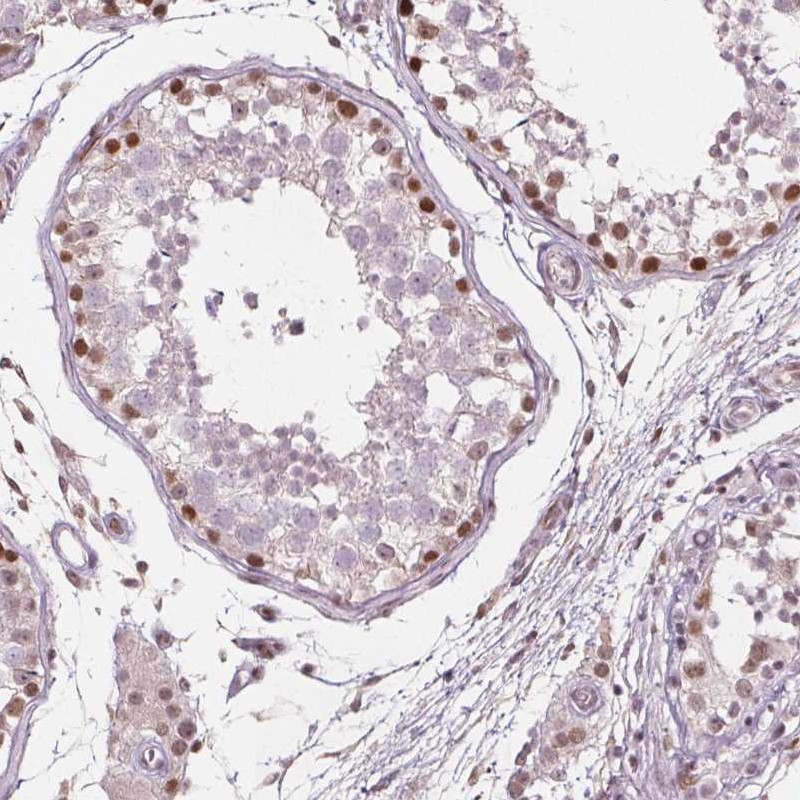

Immunohistochemical staining of human testis shows moderate nuclear positivity in in subset of cells in seminiferous ducts.